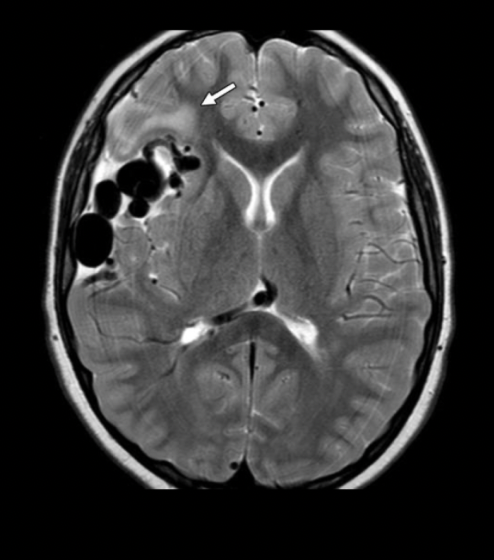

Q

“Maraña en vasos”

Masa con “vacíos de señal”